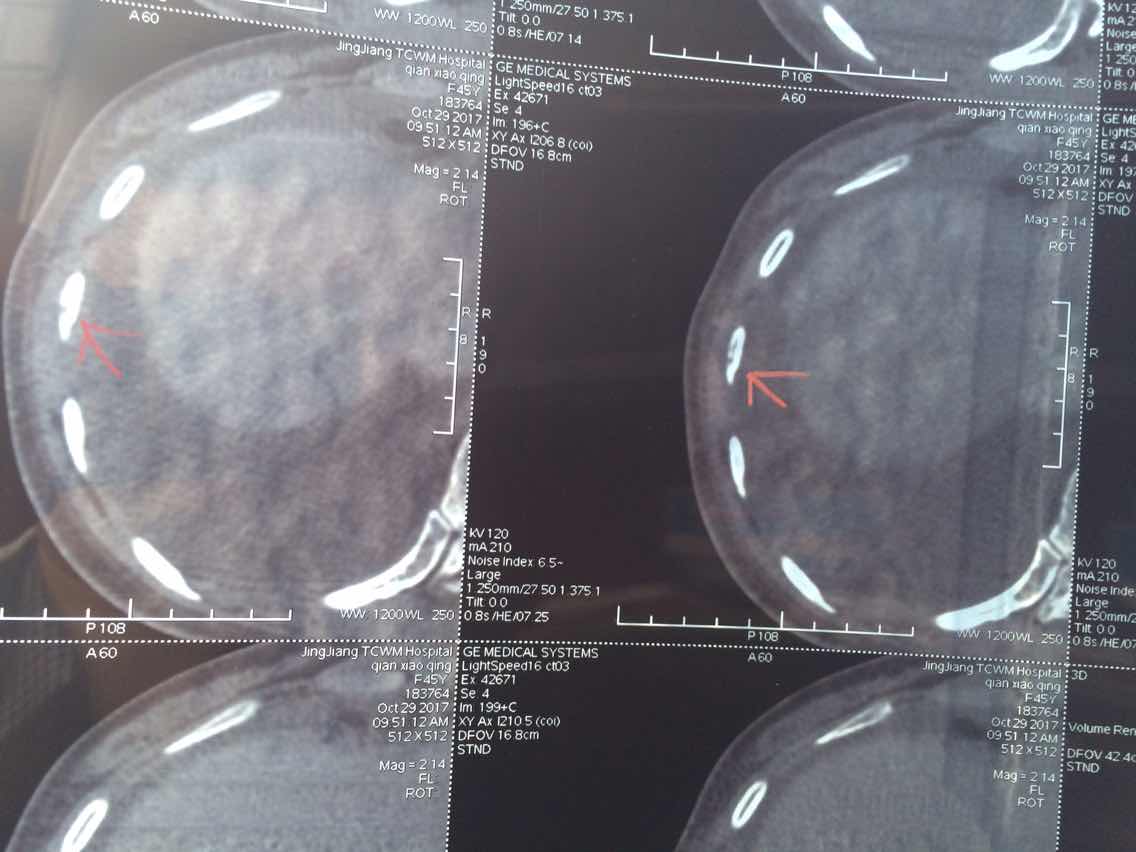

2017.10.29ct

2017.10.29

举报

2017-10-31 10:44:24 有用(0)

回复(0)